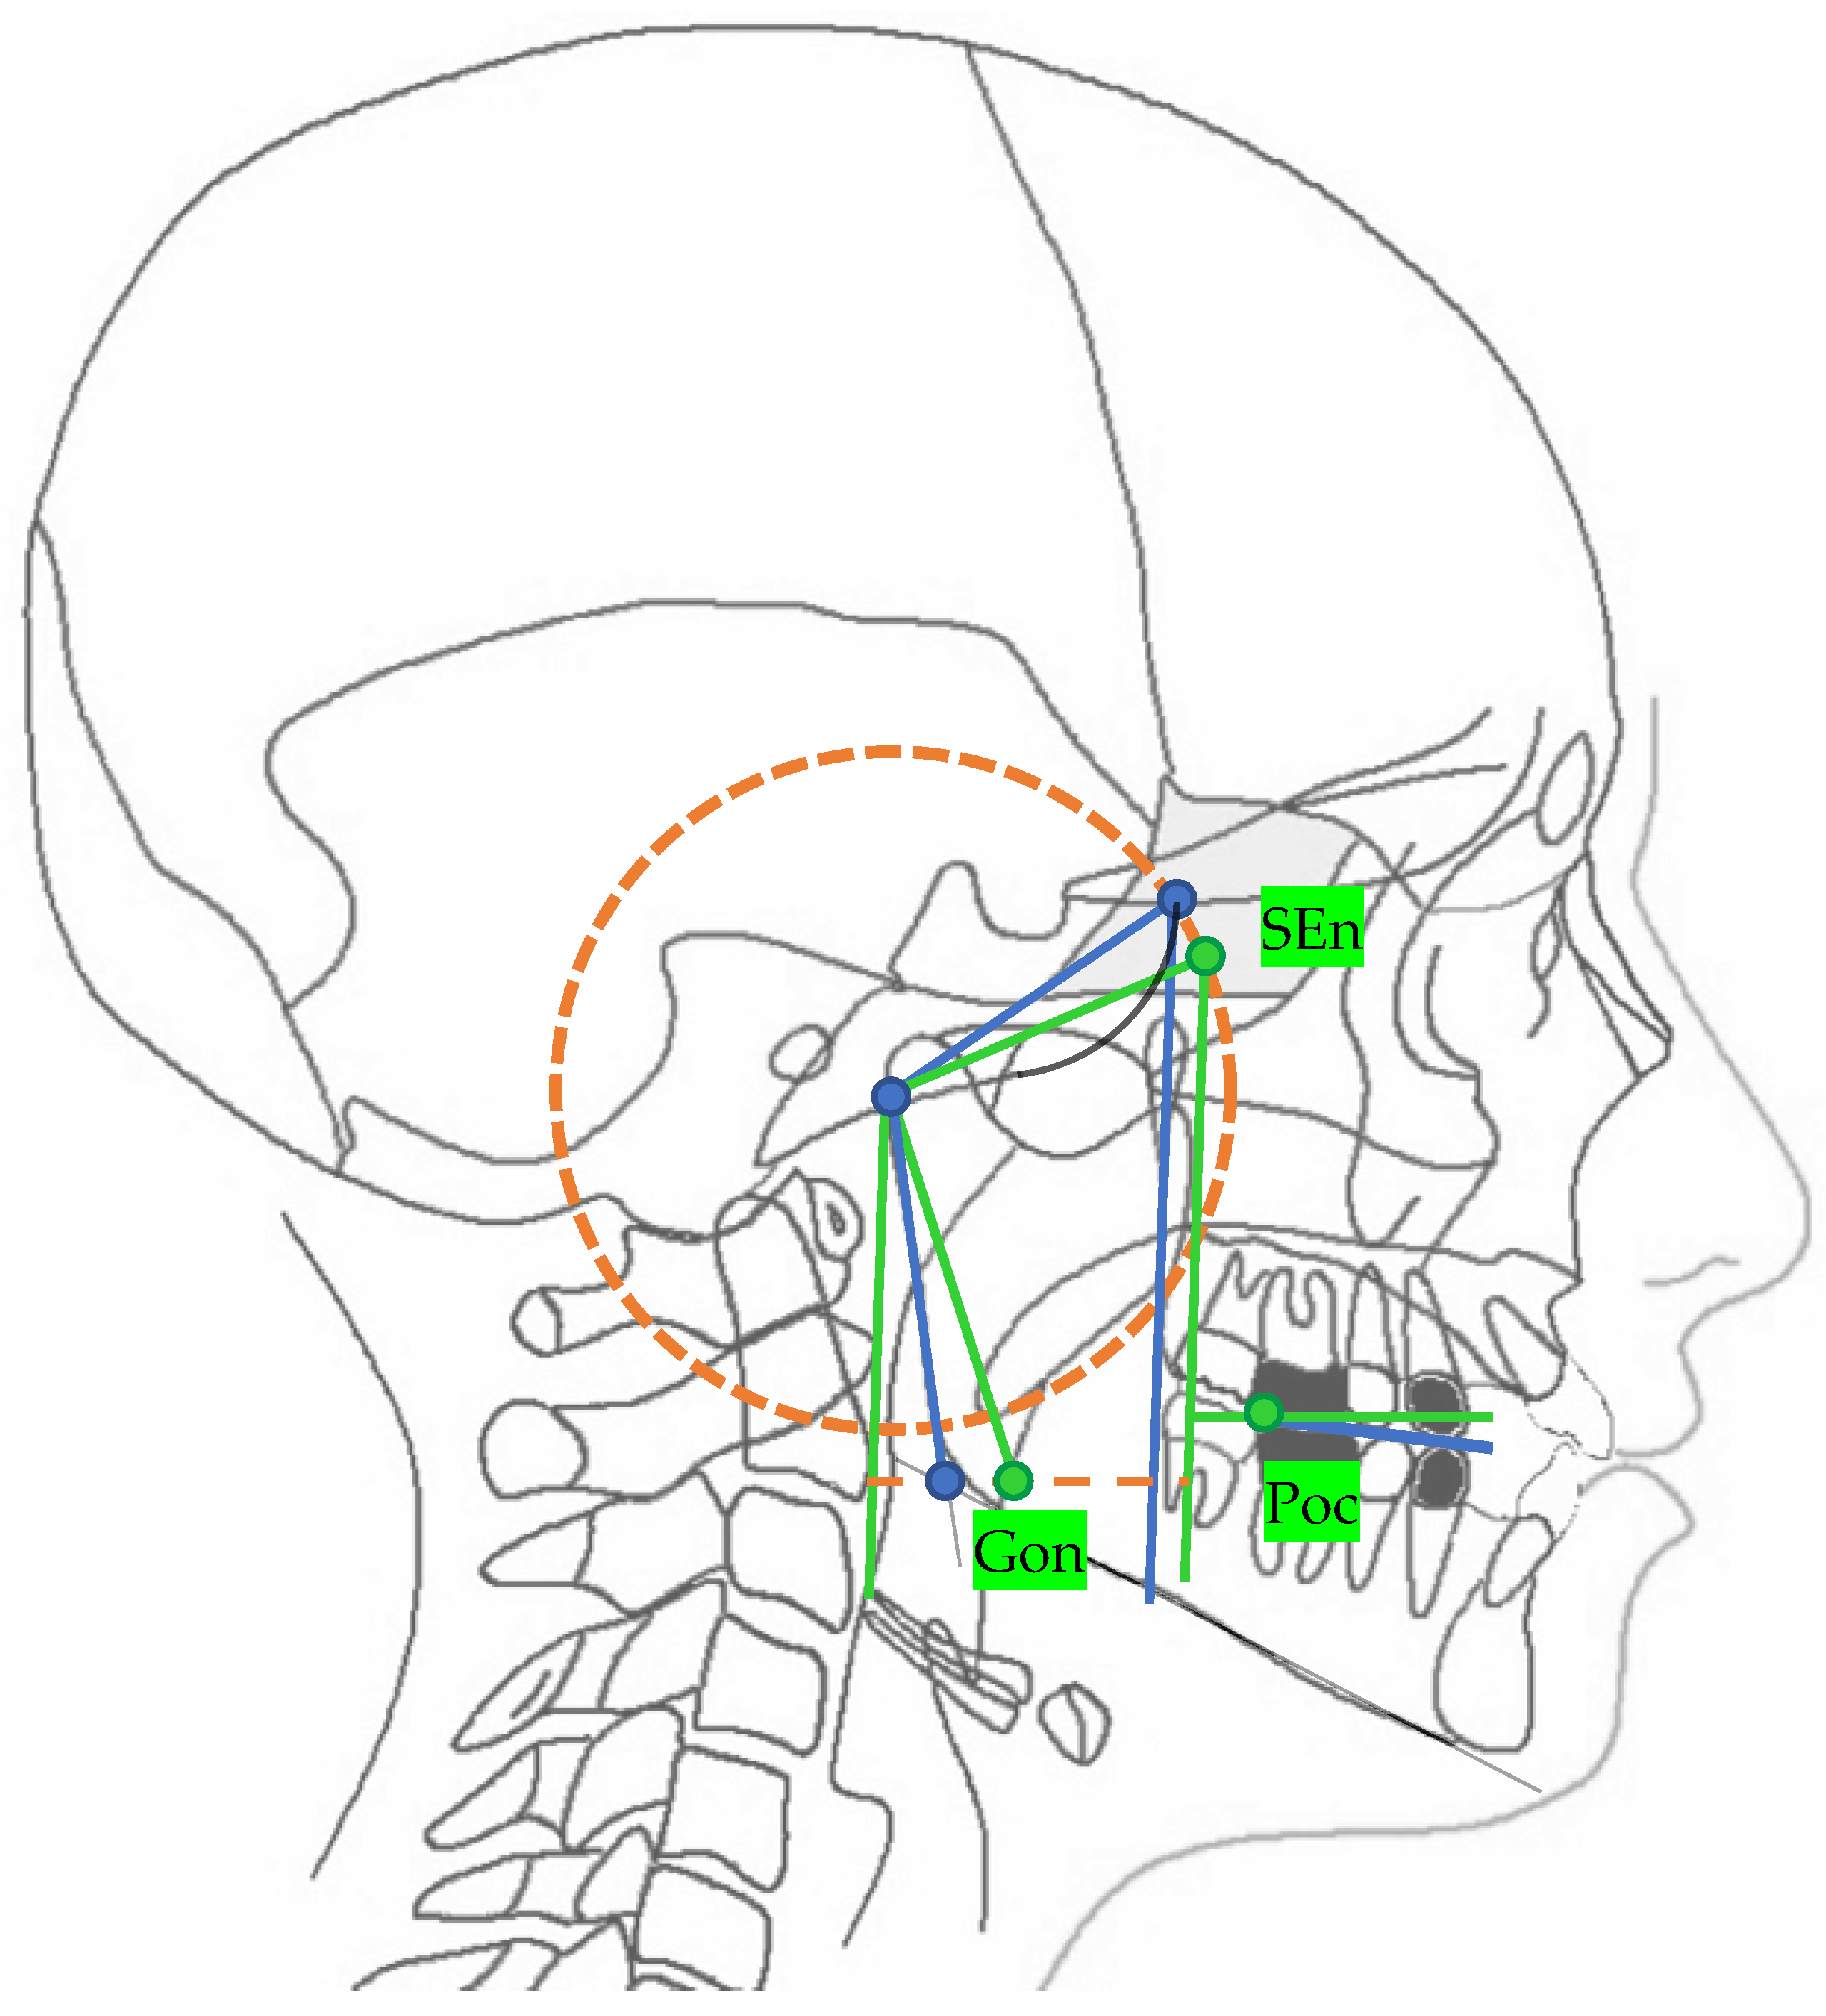

The 2D neutral track analysis compares an individual track with a neutral track [10] The individual track is identified by the following lines: the middle cranial floor, pterygo-mandibular plane, mandibular ramus and functional occlusal plane. All the landmarks and lines of the individual track are explained in Table 1 and all the patient individual planes are shown in Figure 1.

The neutral track (Figure 2) is drawn on the lateral cephalograms identifying the neutral points and planes explained in Table 2.

The only normal value in the neutral track is the angle between the neutral middle cranial floor plane (MCFn) and neutran pterygo-mandibular plane (PMn) which has a value of 40.3° and from which the realization of the neutral track depends.

Figure 1. Points and planes of the 2D individual track. For landmark description, see Table 1.

Figure 2. In green: the 2D neutral track. For landmark description, see Table 2.